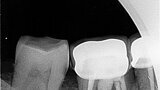

Fig.1a: Pre-op radiograph taken by the referring dentist.